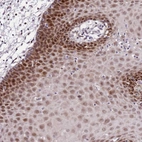

Immunohistochemical staining of human oral mucosa shows strong nuclear positivity in squamous epithelial cells.